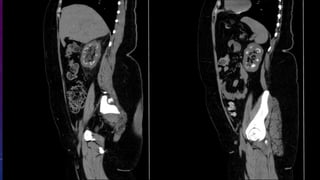

• Failed kidney transplant

• Seminal vesicle / vas deferens calcification

FAILED BILATERAL RENAL TRANSPLANTS

CALCIFICATION

• #62 Failed kidney transplant Seminal vesicle / vas deferens calcification